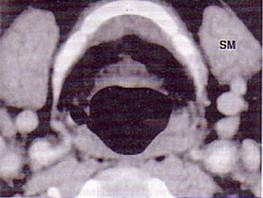

男,55岁,声嘶6年,有长期吸烟史。检查:无呼吸困难。喉镜检查:声带慢性充血,可见右侧声带可见菜花样新生物,右侧声带活动固定,喉部CT检查如下图:诊断...

问题 男,55岁,声嘶6年,有长期吸烟史。检查:无呼吸困难。喉镜检查:声带慢性充血,可见右侧声带可见菜花样新生物,右侧声带活动固定,喉部CT检查如下图: 诊断首先考虑 ( )